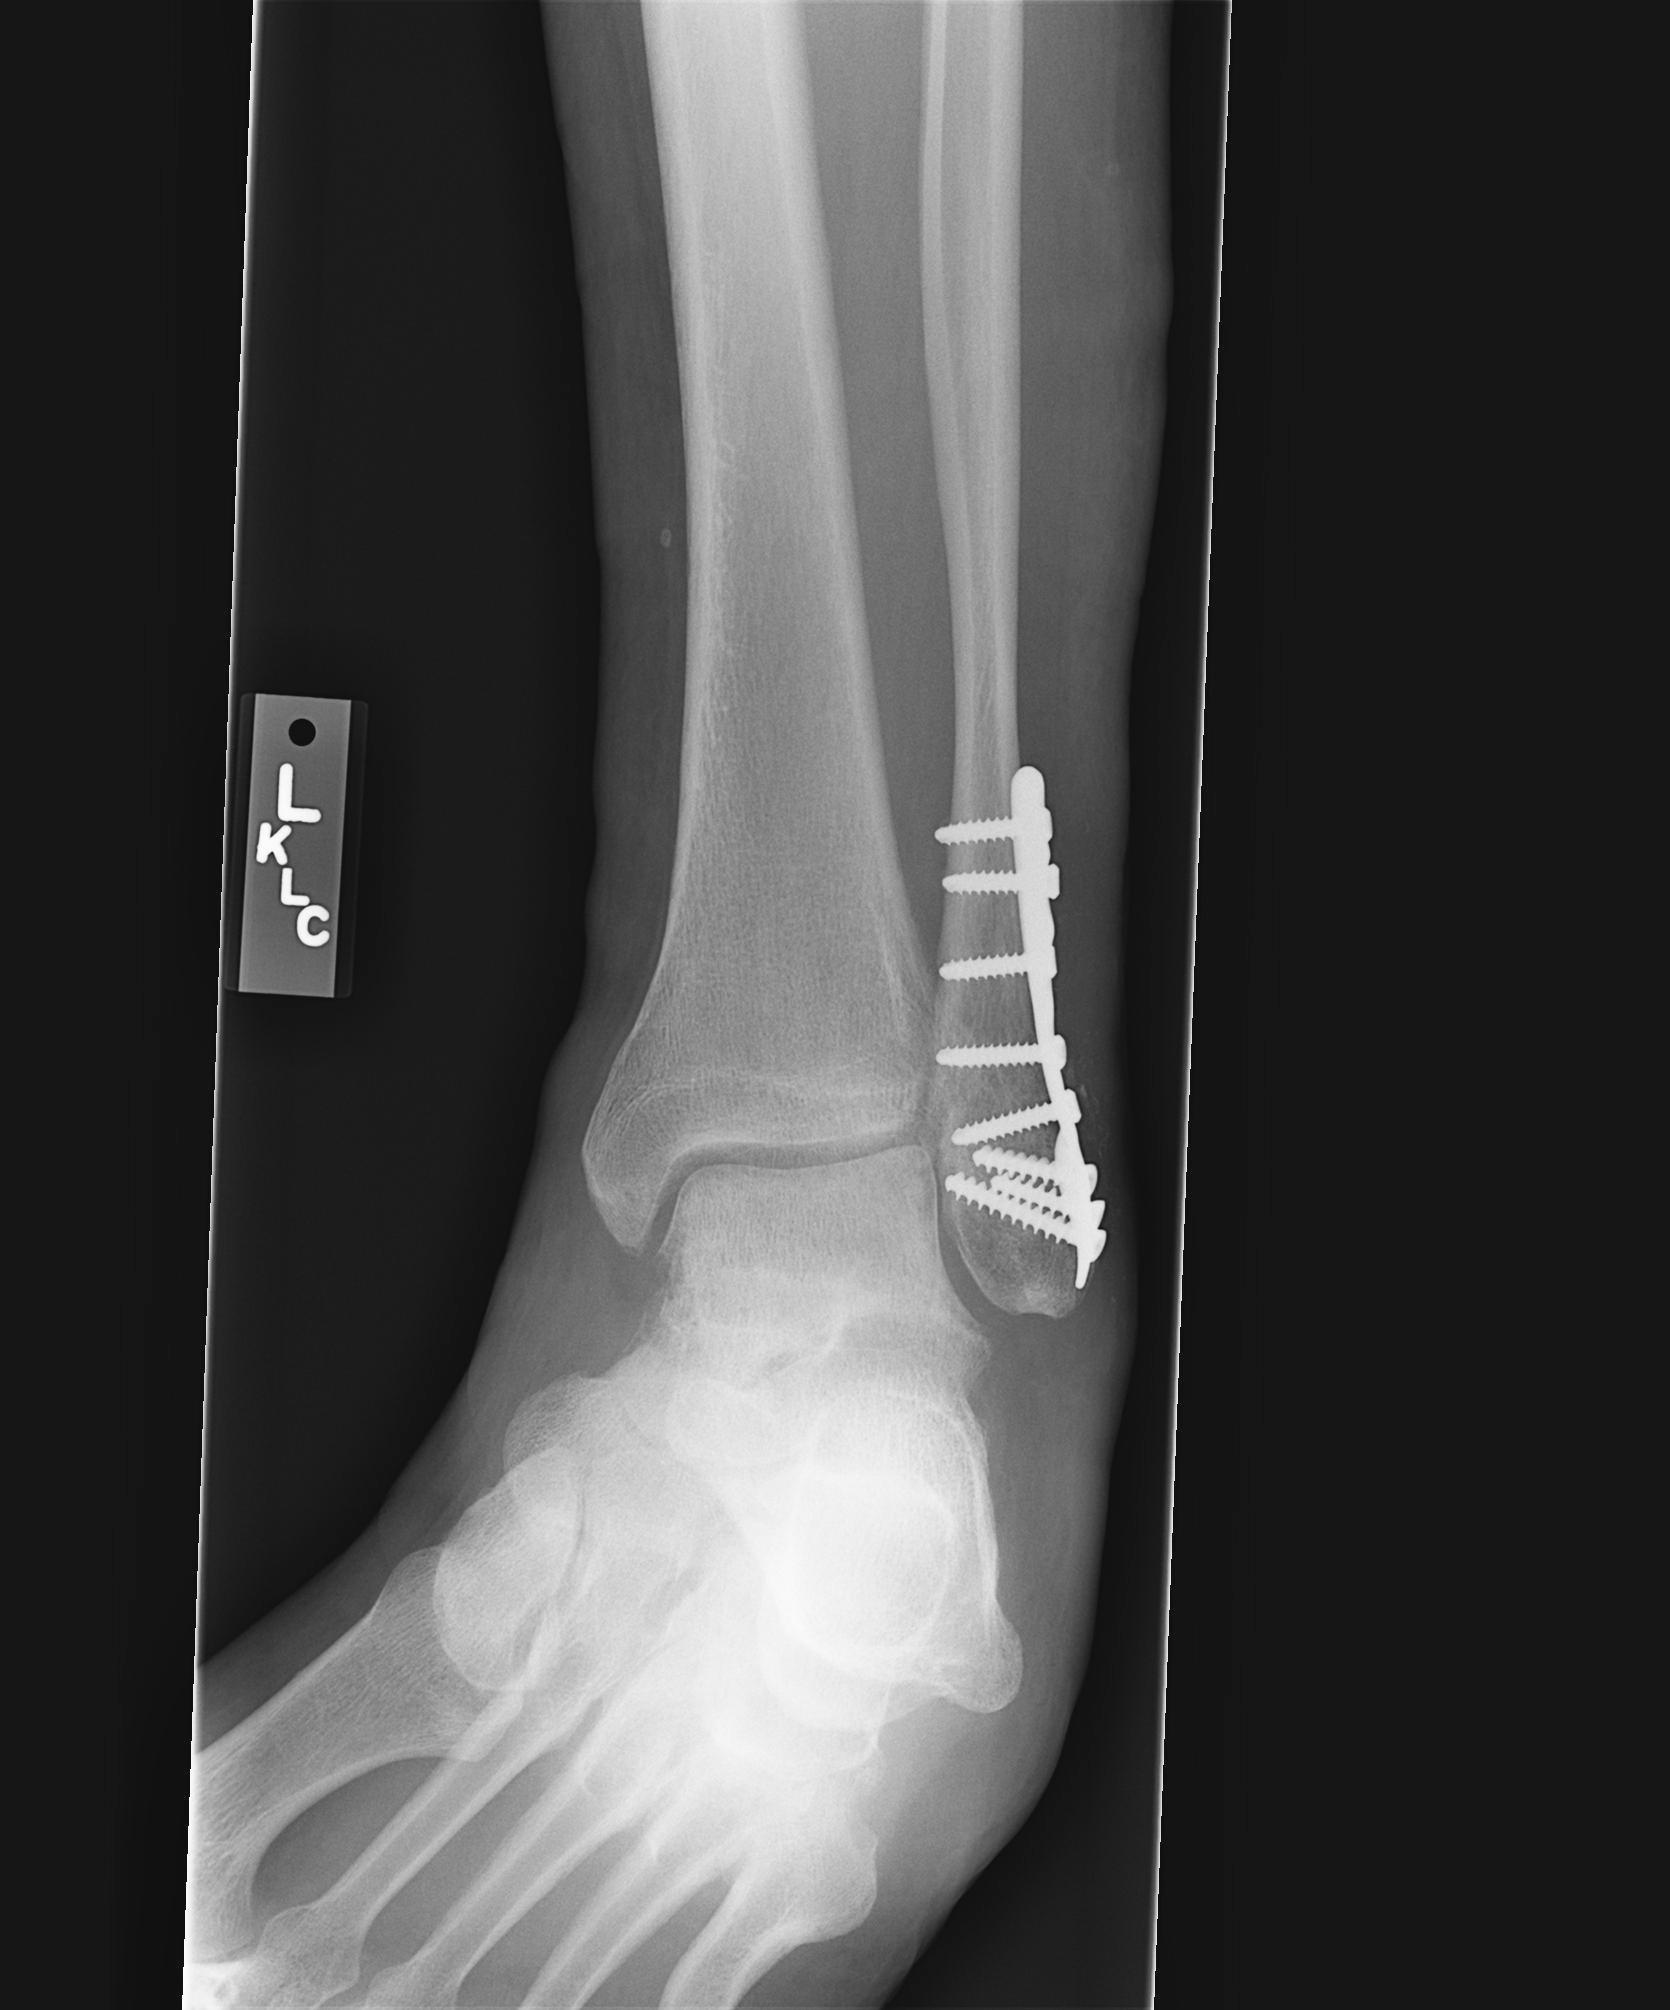

7-17-07

Dr. Visit 8-8-07 - The infection is healing and x-rays show most of the fracture has filled in. Look mid plate and to the left on x-ray #3 to see what is left of the fracture.